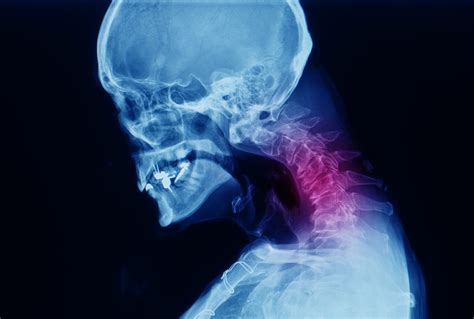

Diagnosing Arthritis in the Neck

Diagnosing arthritis in the neck typically involves a combination of medical history, physical examination, and diagnostic tests. Your healthcare provider may perform the following:

• Imaging Tests: X-rays, MRI, or CT scans to visualize the bones and soft tissues in the neck.

These diagnostic tools help determine the type and severity of arthritis, guiding the appropriate treatment plan.